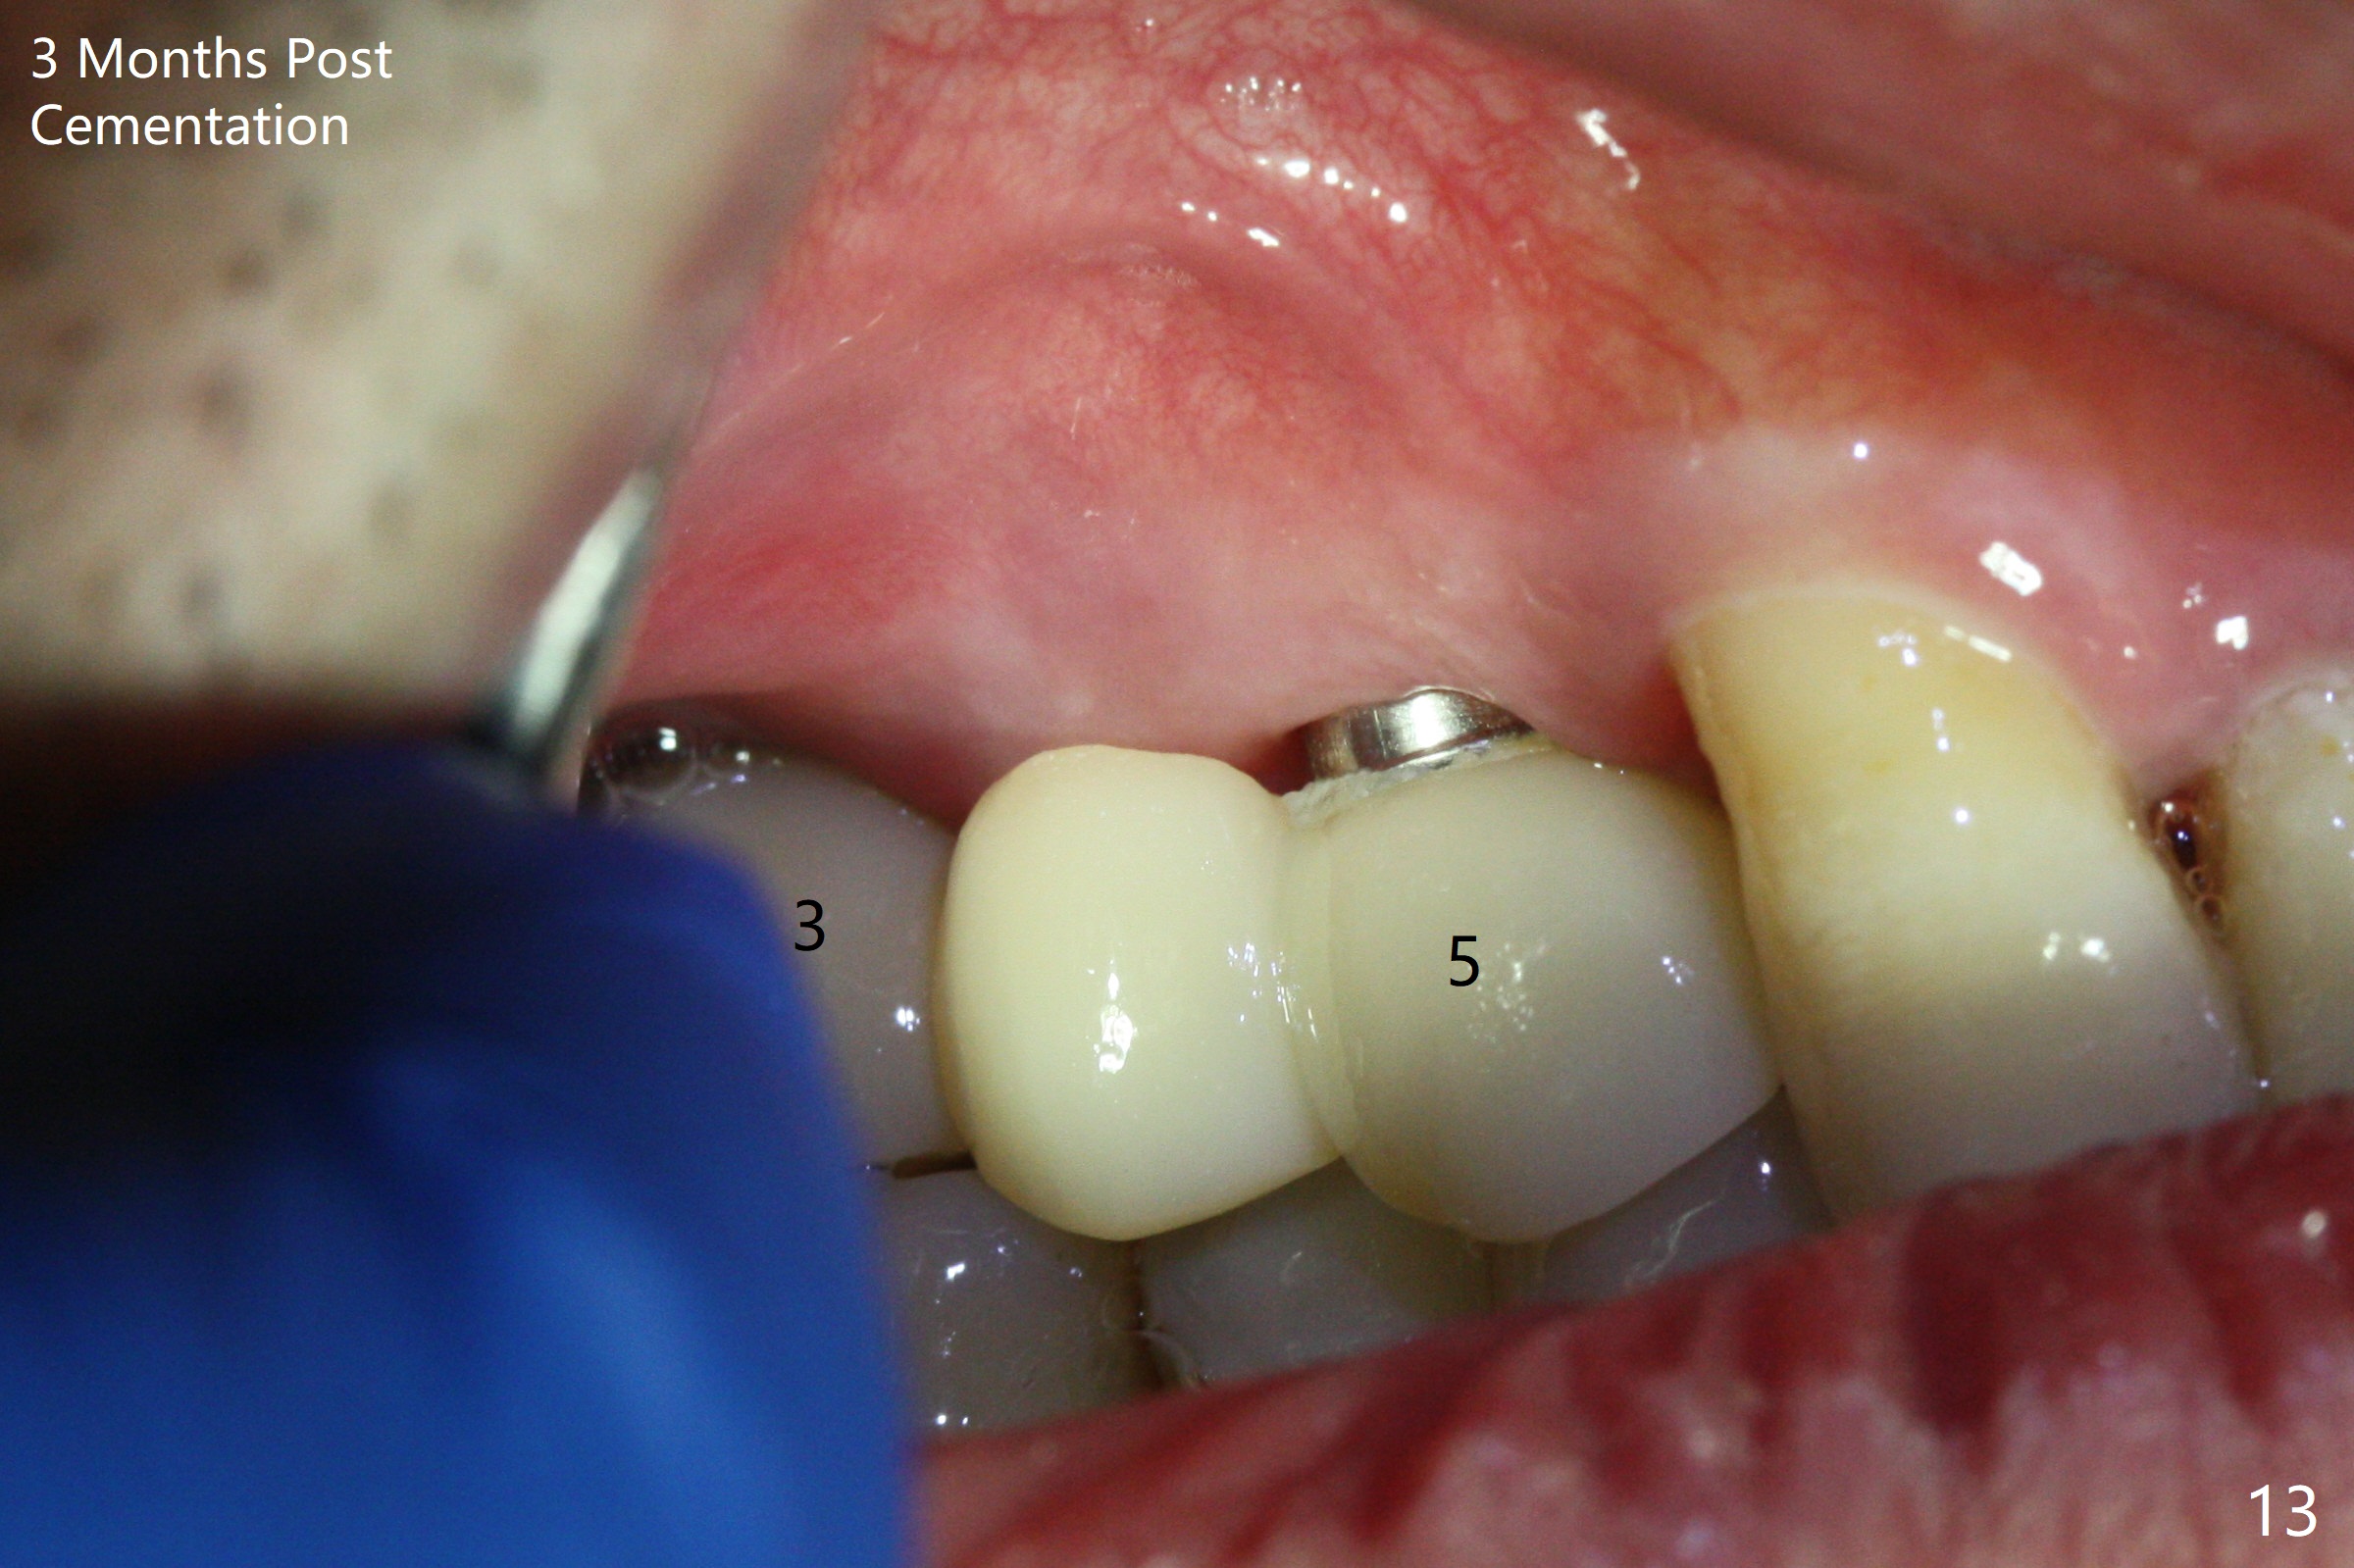

The 36-year-old man (ex-smoker, quit for 4-5 years) insists upon #3 and 5 extraction first for implants, in spite of more severe infection at #7, 14,19,30 (Fig.1-4). The gingiva around #23-26 implants is healthy 3 weeks postop (Fig.5). The initial depths at #3 and 5 are 8.5 mm (bone-level) and 18 mmm (gingiva-level (13 mm (implant length) + 5 mm cuff), respectively. When a drill penetrates the sinus floor, confirm the depth. After use of 3.8 mm drill, 4.5 mm tap drill is inserted at #3 without stability, while a 4.5x13 mm implant is placed at #5 with primary stability (Fig.6,7). Then a 5x11.5 mm is placed at #3 subcrestal proximally after sinus lift with Vanilla graft (without sinus membrane perforation; Fig.8). The implant at #5 is seated ~1 mm deeper (subcrestal mesially (^^); supracrestal distally (^)); allograft is placed around the implants prior to insertion of 6.5x7(5) and 5.5x4(5) mm abutments; last more allograft is added (Fig.9 *, 10). The implants seem to have been osteointegrated 4.5 months postop (Fig.11,12). The gingiva is healthy around the implants without bone loss 3 months post cementation (Fig.13,14).